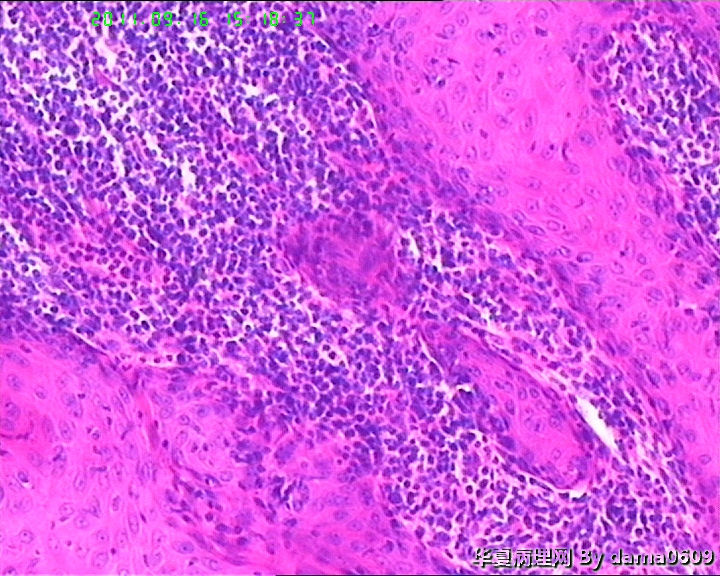

• 背部肿物,急请老师看看!!图2

图2